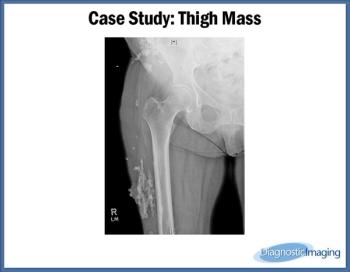

Case History: Woman in 7th decade of life presents with right lateral thigh mass.